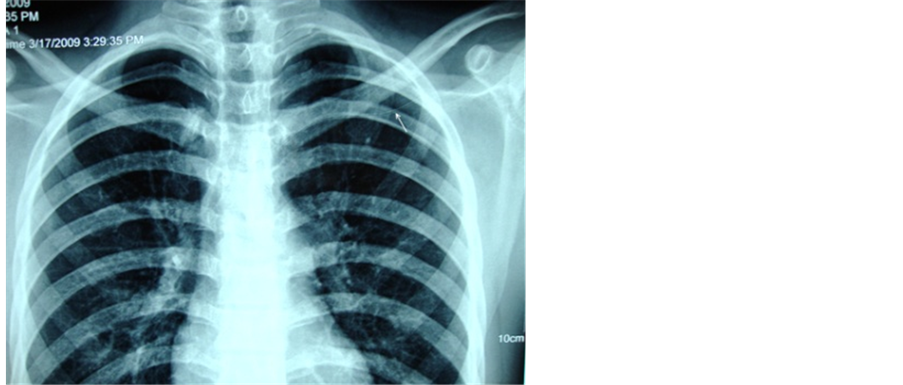

A 17-year boy was admitted with symptomatic anemia in our department. Examination revealed pallor, generalized lymphadenopathy and hepato-splenomegaly. He was investigated and diagnosed to have acute lymphoblastic lymphoma. His base line electrocardiogram (ECG) and echocardiography were normal (Figure 1). He was planned for chemotherapy and a peripherally inserted central venous catheter (PICC) was put through left ante-cubital vein. Procedure was uneventful and peripherally inserted central venous catheter position was confirmed by chest radiography (Figure 2).

Figure 3. CXR showing PICC in place.